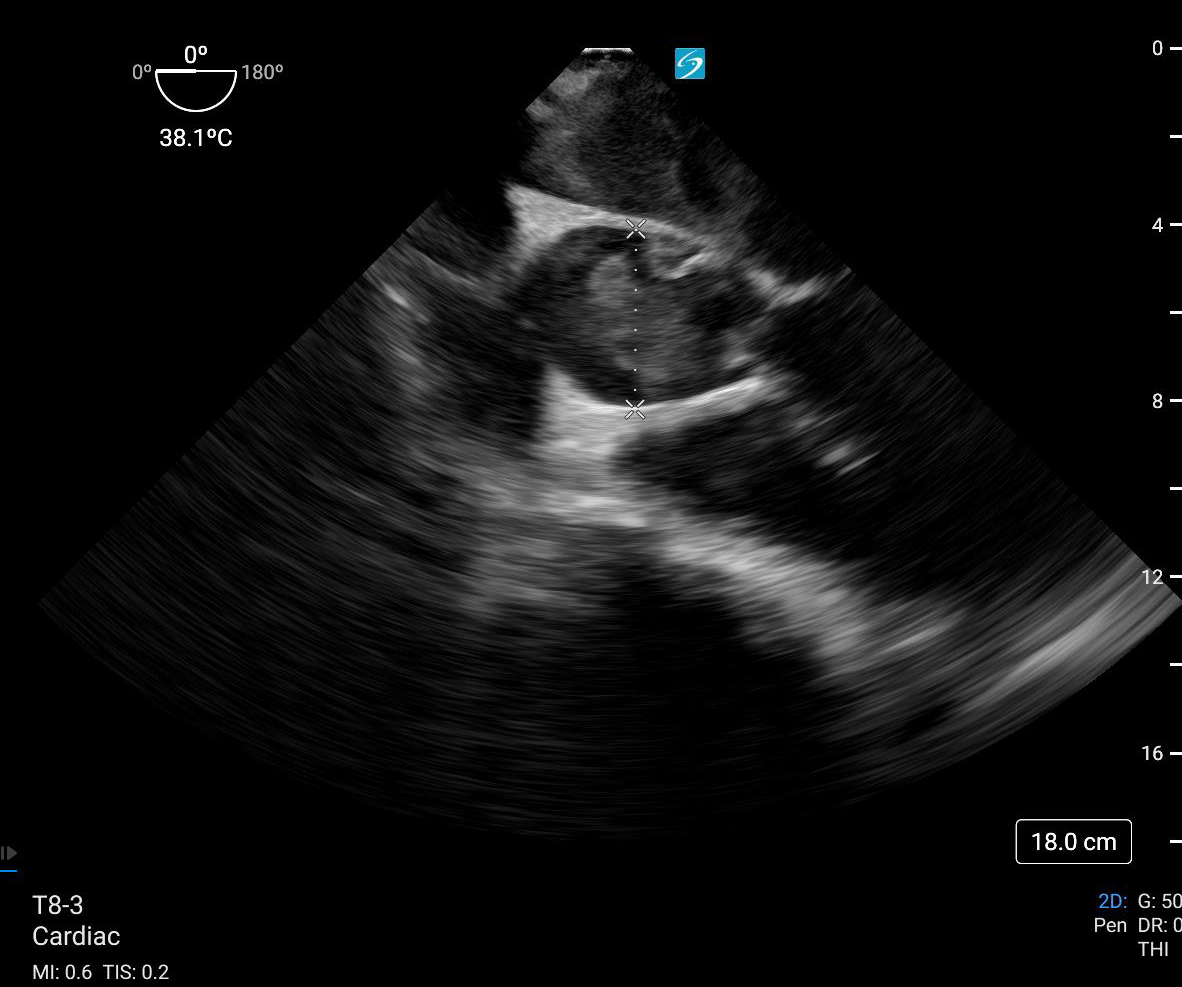

TEE Cardiac Arrest: Aortic Dissection

67 year old male presenting for right arm weakness and chest pain. The patient will become unstable, unconscious, and require intubation. The learner will need to identify the cause and make the appropriate management decisions.